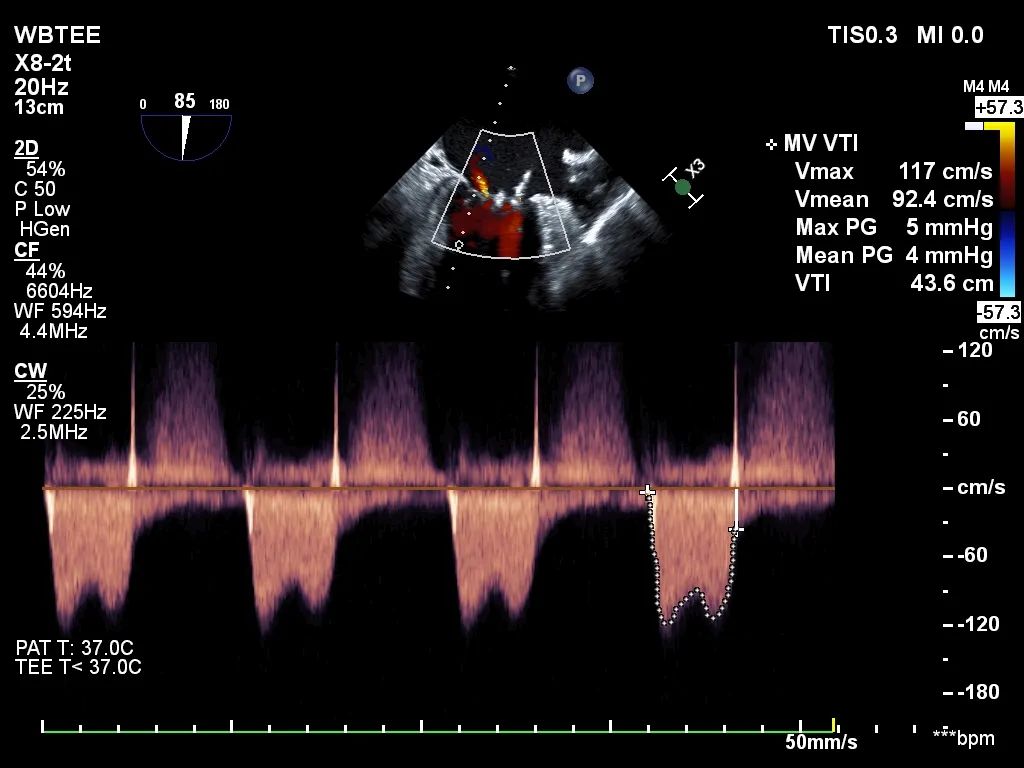

反复测试二尖瓣钳夹的稳定性,超声复查提示二尖瓣夹内侧反流有效改善,外侧仍有部分反流,平均跨瓣压差2mmHg,肺静脉收缩期逆流频谱恢复正向,傅国胜教授团队与超声影像团队充分沟通讨论,计划在二尖瓣夹外侧再置入第二枚二尖瓣夹,遂精准释放第一个二尖瓣夹。

再次反复测试第二枚二尖瓣钳夹的稳定性,超声复查提示二尖瓣反流明显改善,平均跨瓣压差4mmHg。